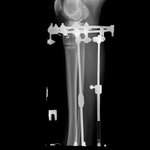

60 дней с момента операции.

Можно снимать аппараты

, но мы подстрахуемся ещё на 2 недели